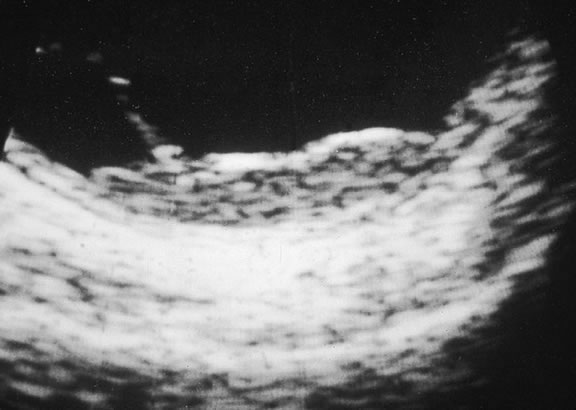

The diagnosis of intraocular metastasis usually is made by slit lamp biomicroscopy and ophthalmoscopy in the patient who has been carefully questioned about a past medical history of cancer. Ancillary techniques such as intravenous fluorescein angiography and ultrasonography often can assist in making the diagnosis. Metastases generally begin to show hyperfluorescence in the late venous phase fluorescein angiography, somewhat later than most melanomas or hemangiomas.48,54 Metastases have many acoustical interfaces because they are composed of nests, cords, and island of tumor cells surrounded by stroma. Hence, they show high internal reflectivity on A scan ultrasonography and appear acoustically solid in B scan, characteristics they share with hemangiomas (Fig. 49). In cases in which the results from other studies are equivocal, cytopathologic examination of material obtained by fine-needle aspiration biopsy may establish the diagnosis.82,83

Fig. 49. B-scan ultrasound, choroidal metastasis. Placoid tumor has high internal reflectivity.